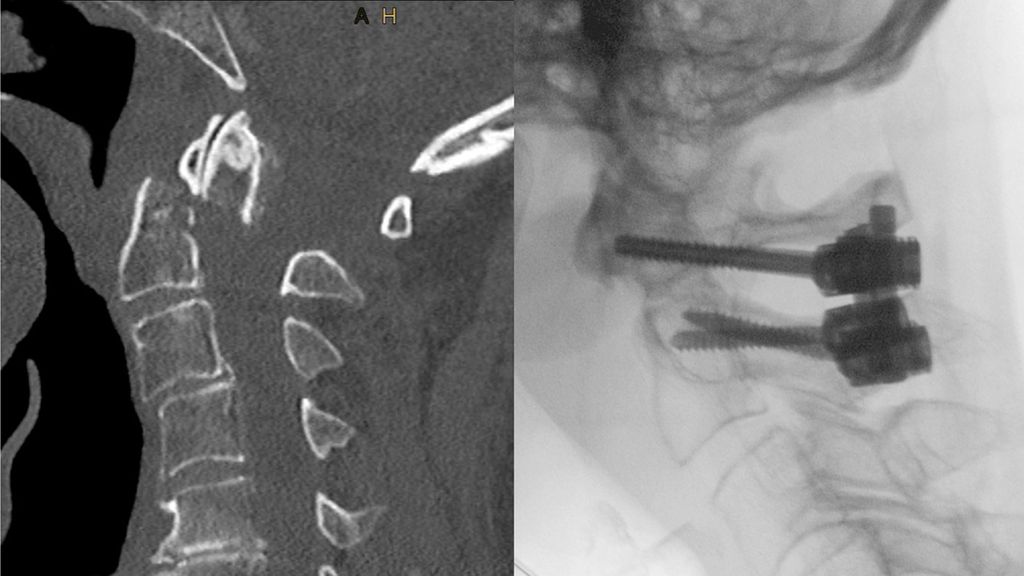

Abb. 2: Dislozierte Densfraktur mit inkomplettem Querschnittssyndrom (A); intraoperatives Bild der C1/2-Stabilisierung (B); postoperative CT-Kontrolle(C)

Die posteriore C1/C2-Instrumentation nach Goel/Harms wird international mittlerweile zur Stabilisierung dislozierter geriatrischer Densfrakturen bevorzugt, da sie biomechanisch eine höhere Stabilität gegenüber der anterioren Densverschraubung aufweist. Dies ist v.a. bei transdentalen Luxationsfrakturen sowie Ankylose der subaxialen HWS vorteilhaft. Diese posteriore Fixierung bietet eine zuverlässige Möglichkeit zur Stabilisierung von Densfrakturen und sehr hohe knöcherne Heilungsraten, geht jedoch mit einer zumindest 50%igen Reduktion der Seitrotation einher. Weitere Nachteile sind die intraoperativ erforderliche Bauchlagerung, der höhere Blutverlust (Blutung aus dem epiduralen bzw. periradikulären Venenplexus bei der Platzierung der C1-Schrauben) und die längere OP-Dauer. Zudem können atypische Verläufe der A. vertebralis die Platzierung der C2- und C1-Schrauben sehr risikoreich oder gar unmöglich machen. In diesen Fällen muss eine Modifikation der Stabilisierungstechnik vorgenommen werden (z.B. Platzierung von kurzen Isthmus- oder Laminaschrauben statt C2-Pedikelschrauben) oder ein anteriores Verfahren gewählt werden.